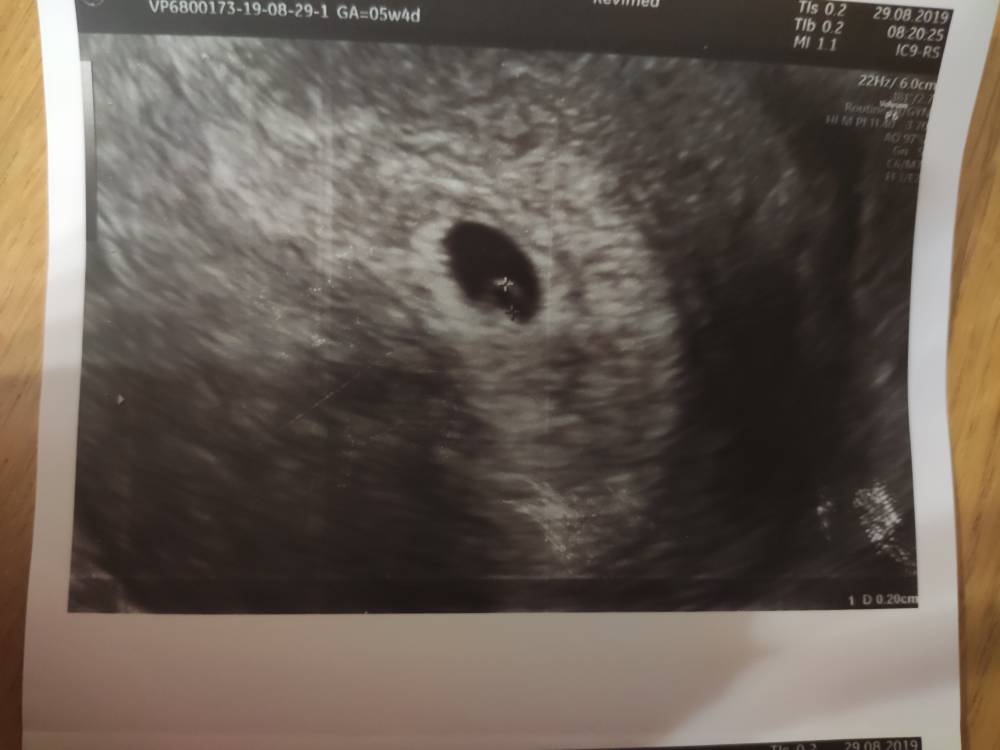

Moje jest z 6+3 ;)